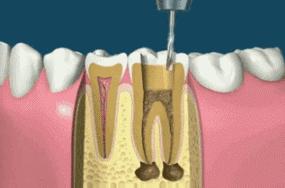

简单来说,根管治疗就是口腔医生把有病变的牙齿打开,然后将牙齿里面发炎、龋坏、坏死的牙髓组织用专业器械清除干净,并把牙髓腔内进行(包含牙髓腔壁)消毒,清洁,最后再用牙胶等物把牙髓腔紧密地封填起来。

因为当牙髓已遭受感染或已经产生不可恢复性伤害时,如果牙髓还有部分活力,就会感到疼痛,为了减轻疼痛的症状,需要将病变牙髓清理干净,防止感染的进一步发展,就需要同时去除牙髓神经,进行根管治疗。

第一张在根管治疗前,拍片可以帮助医生更准确了解牙根的基本情况,以制定治疗计划;

第二张在根管治疗中,可以帮助医生了解治疗的情况,比如根管预备是否到位,方便制定下一步治疗方案;

第三张是在根管治疗结束后,帮助判定根管充填质量,以及治疗效果,发现问题及时补救。